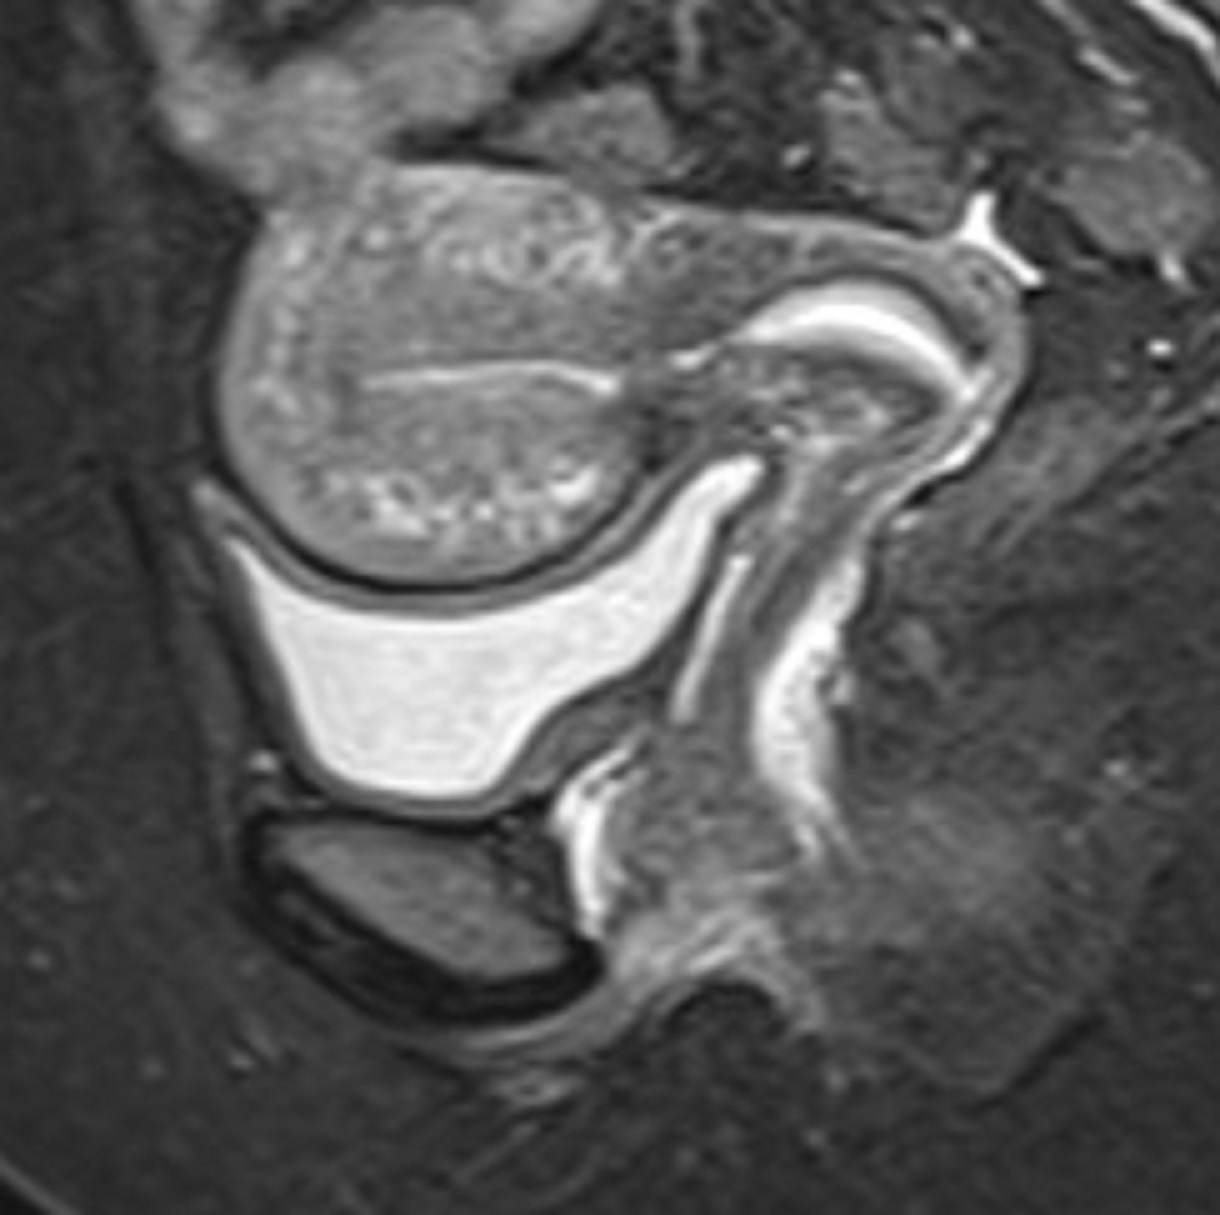

Τα συνηθέστερα συμπτώματα των γυναικών είναι η δυσμηνόρροια, η μηνορραγία και ο πόνος κατά την επαφή (δυσπαρεύνια). Σημαντικό είναι να τονιστεί, ότι η αδενομύωση δεν οδηγείται σε εξαλλαγή σε καρκίνο. Η διάγνωση της αδενομύωσης είναι δύσκολη, καθώς η υπερηχογραφική της εικόνα, πολλές φορές ομοιάζει με αυτή των ινομυωμάτων. Τη λύση έχει δώσει η Μαγνητική Τομογραφία (MRI) η οποία και βοηθάει στη διαφορική διάγνωση της υποκείμενης πάθησης.